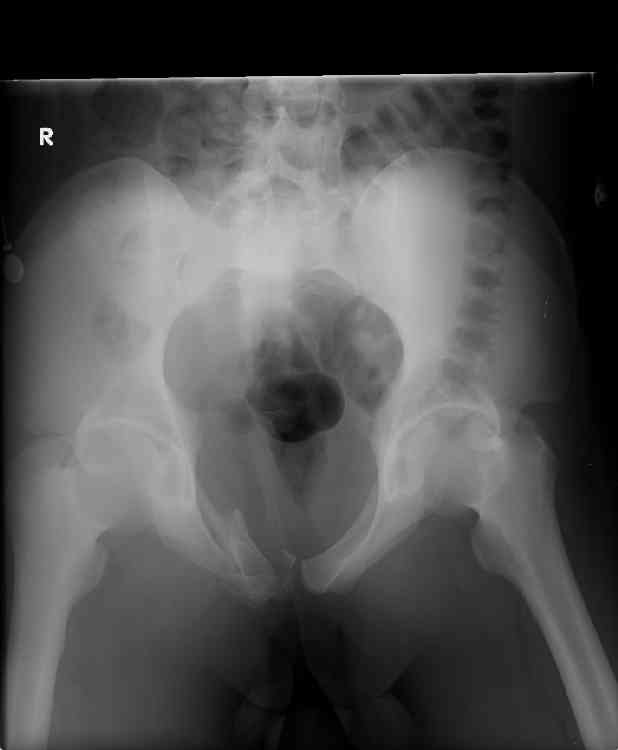

hello, this is a healthy 22yo male. peds vs auto.

no other injuries. has anyone treated these non-operatively? thanks.

dan